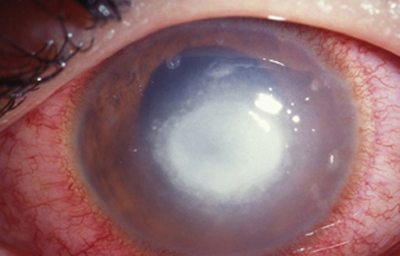

Superficie corneal irregular y grisácea, (Fig. 1, 2) con opácidades granulares en parche y formación de líneas epiteliales elevadas de aspecto granular (Fig. 3), que pueden arborizar dando imágenes de pseudodendritas. Opacidades superficiales satélites. (Figura 4) Inyección ciliar. Ulceración epitelial variante. (Figura 5).

Fig. 2 Síntomas de 25 días evolución